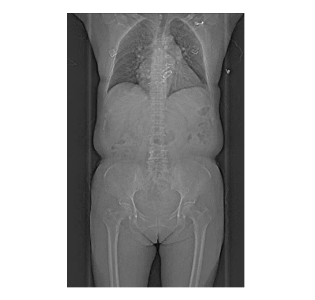

精準醫(yī)療,影像先行。國文醫(yī)療集團影像中心致力于區(qū)域內(nèi)影像水平的提升,不斷引進國際前沿的醫(yī)療設(shè)備和技術(shù),提高診斷的精確度。引進的西門子New Force雙源CT為業(yè)界知名的超高端CT之一,具有巨大的臨床價值:臨床應(yīng)用廣、掃描速度快、圖像質(zhì)量高、輻射劑量低,對全身各個系統(tǒng),特別是冠心病、腦血管疾病、各種腫瘤及全身多發(fā)性創(chuàng)傷等成像質(zhì)量高、診斷準確率高,同時有利于各種疾病的預(yù)后評估。

采用雙球管+雙探測器設(shè)計,掃描速度達0.25秒/圈,1秒完成全身大血管成像,擺脫心跳、呼吸等運動偽影、金屬植入物偽影的干擾,極大程度減低了控制心率的要求和屏氣的時間。冠脈CTA成像不受心率限制,其他CT做冠脈CTA檢查,都要求心率70以內(nèi),發(fā)現(xiàn)超過90的心率就不繼續(xù)檢查了,但是對于雙源CT,就沒有這個限制,心率超過100的患者,仍然可以檢查,且擁有高成功率,并且對于心率二聯(lián)律的患者,機器可自行識別,確保患者的清晰成像。

支持“無禁忌”全身檢查,尤其適合急癥患者(如急性胸痛、胸痛三聯(lián)征)的“一站式”快速檢查,為搶救贏得黃金時間。

搭載Cinematic VRT三維重建技術(shù),立體還原器官、全身大血管解剖結(jié)構(gòu),對血管狹窄、斑塊性質(zhì)一目了然。 智能分析組織灌注(心肌/腦/肺),提升診斷效率與準確性。

檢查無需藥物控制心率或長時間準備,減少等待焦慮。80cm超大掃描范圍,肥胖或特殊體位患者亦可輕松完成檢查。